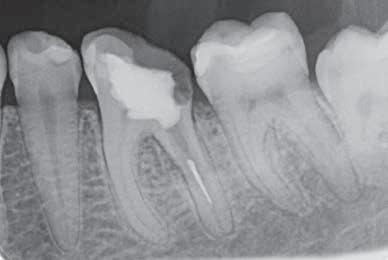

En patient får foretaget en rodskylning på grund af smerter efter en udrensning i forbindelse med en rodbehandling af 6+. Efter skylningen renser tandlægen med en rodfil i samme størrelse som den, der blev brugt til udrensningen. Rodfilen knækker dog undervejs så højt oppe i kanalen, at den ikke kan fjernes.

LÆRING

Efter en nylig rodbehandling kan man med rimelighed forvente, at rodkanalen er glat og fri for grater, når der anvendes en rodfil af samme størrelse til at rense. Man skal dog

være opmærksom på ikke at presse rodfilen højere op i kanalen end rodmålet (målefejl).

Det er vigtigt at have overblik over, hvor mange gange en rodfil har været anvendt og tjekke den for svaghedstegn, fx vrid eller buk, før den bruges igen. Vurder altid, om filen fortsat er egnet til tandbehandling, og udskift den i tide, før metaltræthed eller brud opstår.